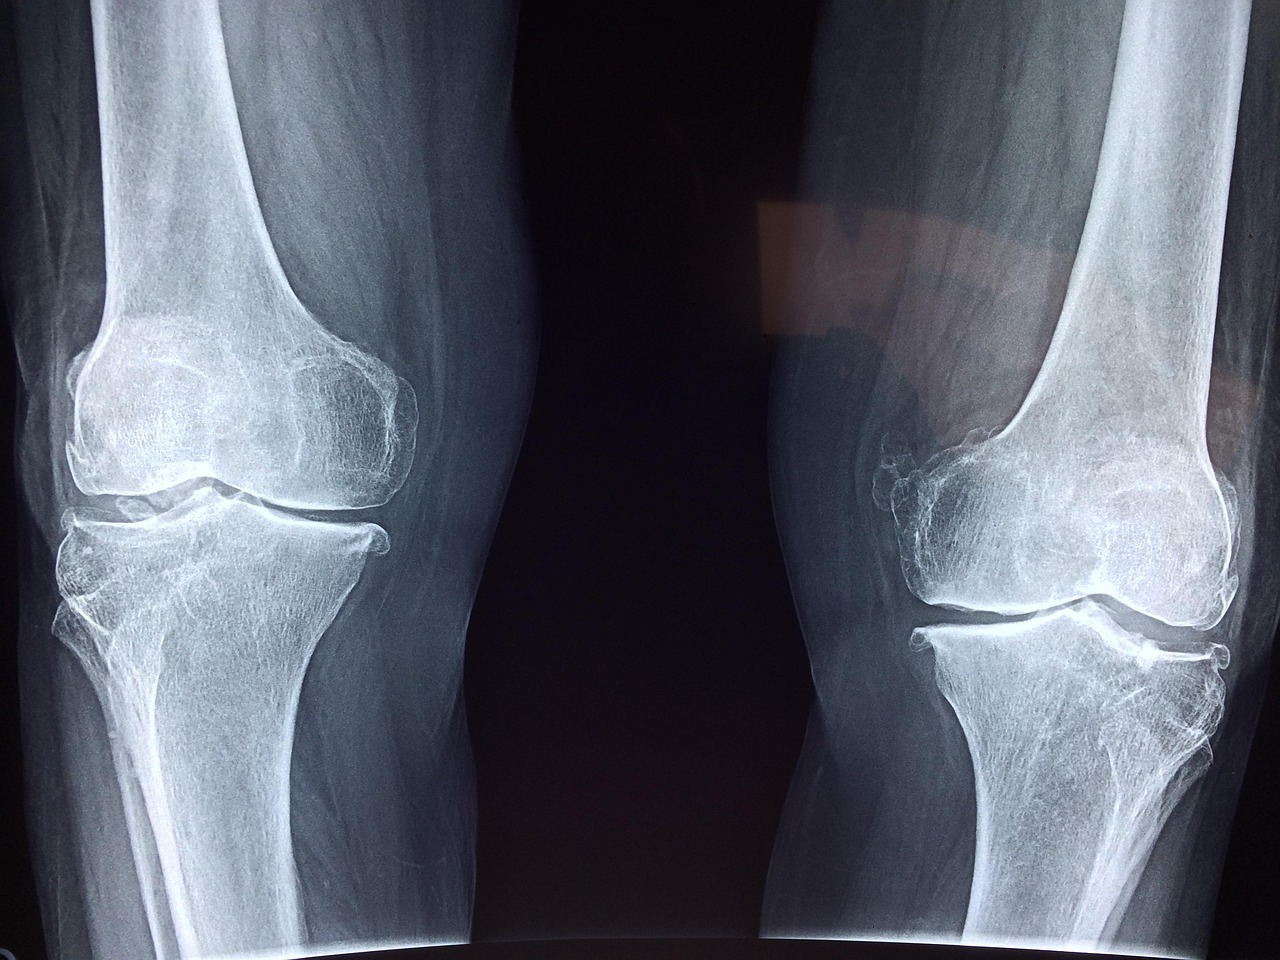

Cartilage is vital for joint health, acting as a cushion to prevent bones from rubbing against each other. Essential nutrients play a role in maintaining and regenerating cartilage, which is particularly important as we age. These nutrients can help reduce inflammation and promote cartilage synthesis, leading to improved mobility and reduced pain. Among the critical nutrients, omega-3 fatty acids stand out for their anti-inflammatory properties. These fats, found in fish oil and flaxseed, can aid in promoting joint health through their ability to inhibit inflammatory markers. Another important nutrient is glucosamine, which is often used in supplement form to help regenerate cartilage. Research suggests that glucosamine may stimulate the production of cartilage components, thereby supporting joint function. Chondroitin sulfate is also essential, often paired with glucosamine in supplements; it helps retain moisture in the joints, thus enhancing lubrication. Vitamins C and D play a role in collagen formation, crucial for cartilage strength and repair. Together, these nutrients provide a robust foundation for your joint health, significantly improving the quality of life for those suffering from joint pain or degeneration.